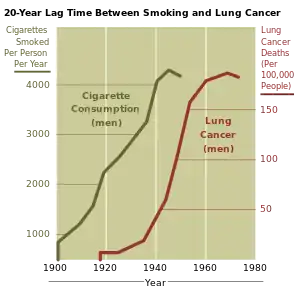

Smoke, or any partially burnt organic matter, contains carcinogens (cancer-causing agents). The potential effects of smoking, such as lung cancer, can take up to 20 years to manifest themselves. Historically, women began smoking en masse later than men, so an increased death rate caused by smoking amongst women did not appear until later. The male lung cancer death rate decreased in 1975—roughly 20 years after the initial decline in cigarette consumption in men. A fall in consumption in women also began in 1975[218] but by 1991 had not manifested in a decrease in lung cancer–related mortalities amongst women.[219]